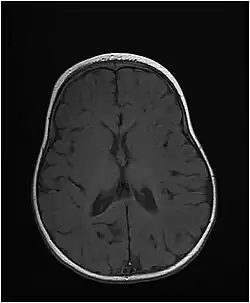

Заболевание начинается с рождения либо в раннем младенческом возрасте, проявляясь такими симптомами, как микроцефалия, низкий рост, задержка психического развития. У пациентов развиваются эпилептические судороги, которые иногда с трудом поддаются контролю. На снимках мозга наблюдается задержка образования миелиновой оболочки либо потеря миелина.